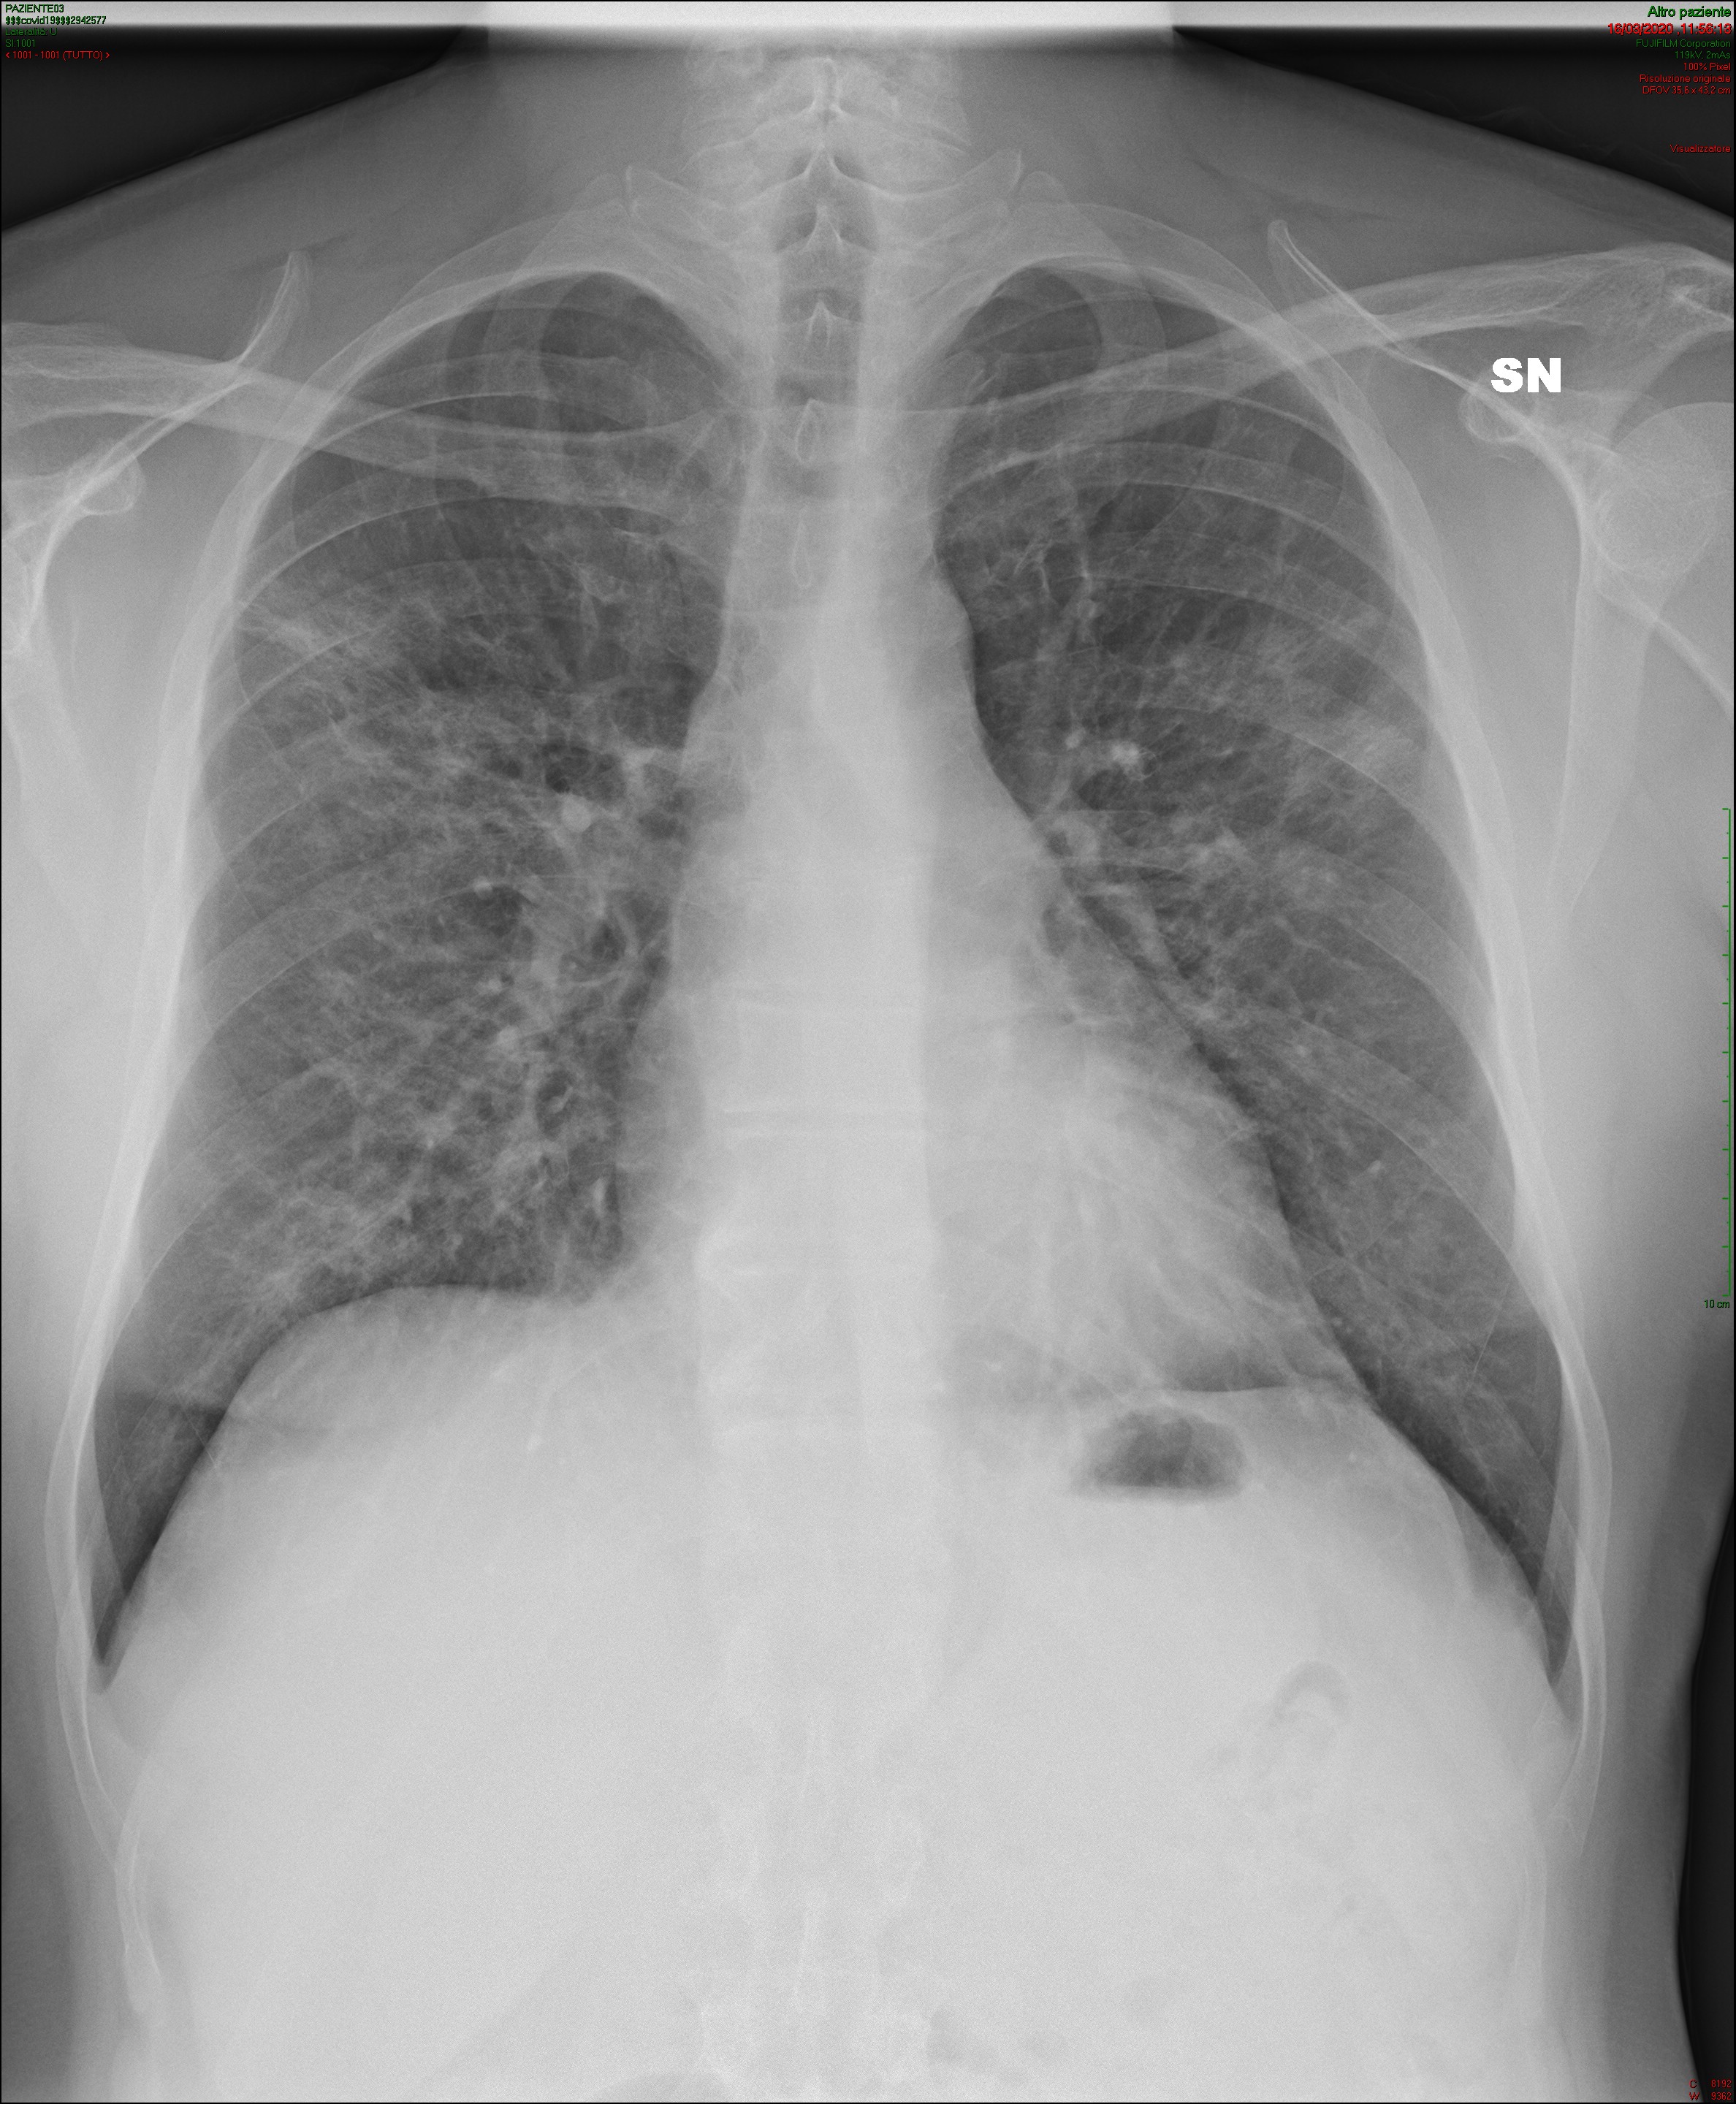

(b) Lungs of a COVID-19 infected patient.

Figure 1: Examples of PA chest X-rays in the data-set in Figures 1(a) to 1(d), and distribution of the diagnoses based on the PA chest X-rays in Figure 1(e).